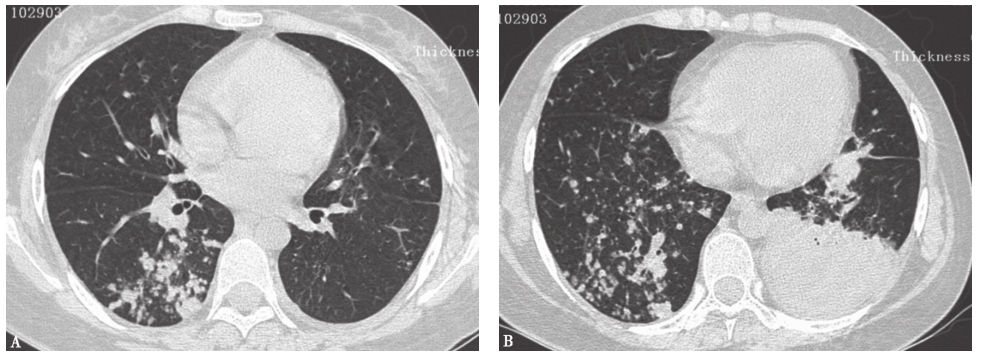

侵袭性真菌感染指侵入人体组织、血液,并在其中生长繁殖导致组织损害、器官功能障碍、炎症反应的病理改变及病理生理过程。真菌感染常继发于免疫功能低下和粒细胞缺乏状态。可造成胸部影像学表现为多发结节影的致病真菌包括念珠菌、曲霉、隐球菌等。肺念珠菌病根据感染途径分为原发(吸入)性念珠菌肺炎和继发性念珠菌肺炎(指血源性播散引起的肺部病变)。后者(血行播散型真菌感染)的全身症状有畏寒、发热、心动过速,甚至出现低血压、休克、呼吸衰竭等,胸部影像学表现可为阴性,少数患者影像学表现为肺间质病变,亦可呈粟粒状阴影或趋于融合(图5)。隐球菌感染者胸部影像学表现多见单发或多发结节或团块影,常位于胸膜下,直径1~10cm,边缘光整,也可边缘模糊或有小毛刺(图6A),弥漫性粟粒状阴影或肺间质性病变较少见,可发生在获得性免疫缺陷综合征(acquired immunodeficiency syndrome,AIDS)患者(图6B)。侵袭性肺曲霉菌病(invasive pulmonary aspergillosis,IPA)可分为气道侵袭性曲霉菌病和血管侵袭性曲霉菌病。前者CT表现为小叶中央性小结节和树芽征,支气管周围实变影(图7);后者CT特征为多发结节及周围晕征、空洞和空气半月征。本例患者无免疫功能低下或粒细胞缺乏等高危因素,病程较长,无发热、咳嗽、咯血等感染症状,故患真菌感染可能性不大。

图5念珠菌肺炎胸部CT表现

肺移植术后因留置导管出现发热,经培养确诊念珠菌肺炎。胸部CT可见双肺弥漫随机分布的结节影

图6隐球菌肺炎胸部CT表现

A.男性患者,73岁,反复发热、咳嗽、咳痰2年,再发1个月,病理确诊为隐球菌肺炎,胸部CT可见双肺多发高密度斑片影,部分呈结节状改变,伴双侧少量胸腔积液;B.男性患者,65岁,反复发热伴消瘦5个月,感染HIV,病理诊断为播散性隐球菌肺炎,胸部CT发现双肺呈随机分布的弥漫粟粒性结节